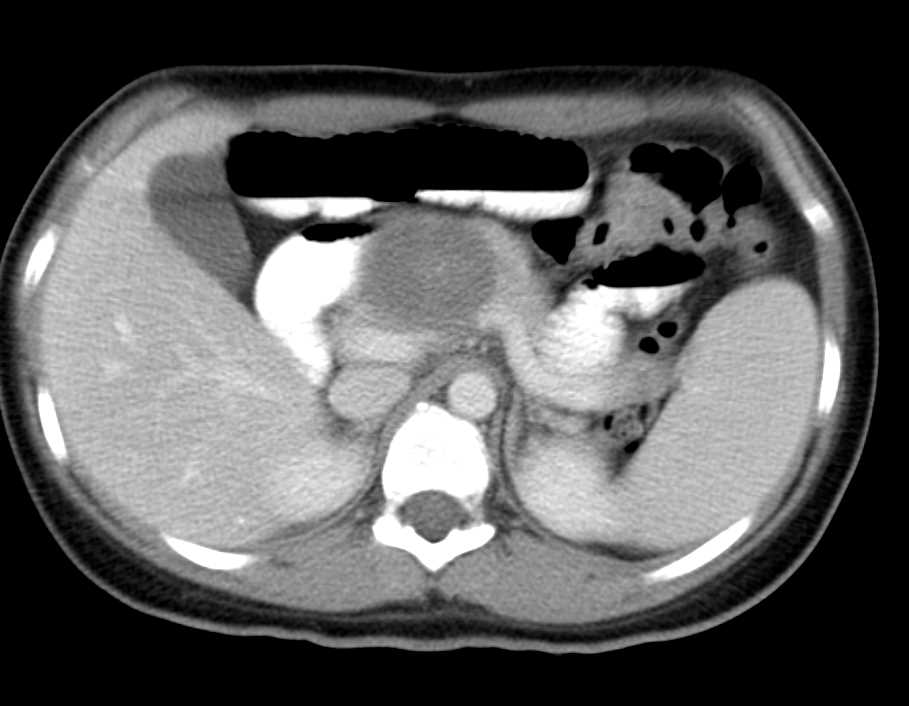

Serous Cystadenoma